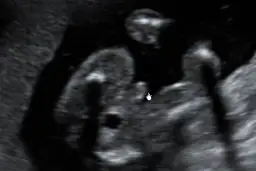

Jeśli zależy Ci na pewności, najlepszym rozwiązaniem są badania medyczne. USG to najczęstsza metoda, która pozwala określić płeć dziecka z dużą dokładnością. Wykonuje się je zwykle między 18. a 22. tygodniem ciąży.

USG to standardowe badanie, które pozwala określić płeć dziecka. Wykonuje się je zwykle w drugim trymestrze ciąży. Dokładność tej metody wynosi około 95-98%, co czyni ją jedną z najbardziej wiarygodnych.

Warto jednak pamiętać, że wynik zależy od doświadczenia lekarza oraz jakości sprzętu. W niektórych przypadkach, np. gdy dziecko ułoży się w niewygodnej pozycji, określenie płci może być trudniejsze.